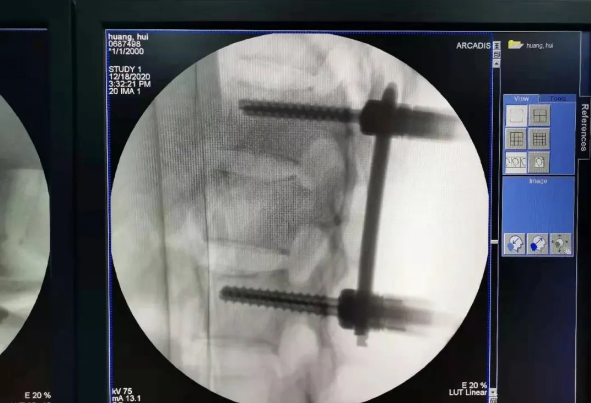

患者為22歲年輕女性,因車禍致骨盆骨折。骨盆骨折是一種復雜的創傷,傳統手術方式需要比較大的切口,而且骨盆內有大量復雜血管和神經,手術難度和風險極大,是很多骨科醫生的禁區。

在傳統骨科手術中,反復使用X線透視,有時須經常調整或更改手術固定方式,常常需要多年的臨床經驗積累,也難免意外頻發,畢竟人眼判斷和X線透視單平面觀察的局限性是客觀原因。

我國自主研發的天璣?骨科手術機器人,是針對骨骼硬組織的先進技術,已經獲得國際認可,能夠開展脊柱全節段 (頸椎、胸椎、腰椎、骶椎) 疾病、骨盆和四肢等骨折、骨腫瘤以及關節導航等手術。相比傳統手術,機器人輔助手術具有手術創傷小、出血少、并發癥少、康復快的優勢。同時,由于不需通過反復透視來確定置釘位置,從而能減少術中輻射,大大降低患者輻射危害,且手術過程中,由機器人與主刀醫師共同完成手術,大大增加了手術安全性。

在南昌市第一醫院廖琦教授帶領下,由創傷骨科團隊借助天璣?骨科手術機器人為患者“量身定做”最理想、最安全的教科書般的通道,完美安全微創完成手術,并且手術時間明顯縮短,真正做到“指哪兒打哪兒”!更讓患者放心的是,天璣?骨科手術機器人的“穩定手”機械臂進行精準定位,不用反復探尋。

由于天璣?骨科手術機器人的精準及高效,可以使手術時間明顯縮短,因此在骨盆骨折手術后,在廖琦教授指導下,脊柱外科團隊利用天璣?骨科手術機器人同樣為20歲女性腰椎骨折患者“量身定做”最理想、最安全的教科書般的通道,完美安全微創完成手術,手術不僅時間縮短,并且出血和透視減少。